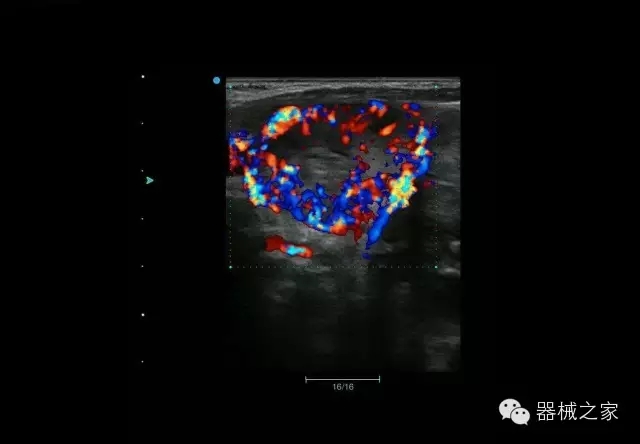

臨床圖片賞析

睪丸低速血流